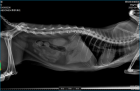

【图片】求专业人士帮忙看下猫咪化验单和片子